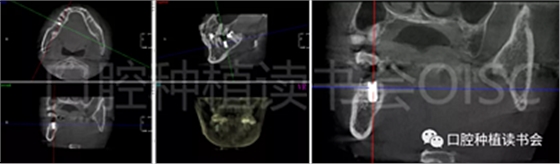

術前CBCT(美亞光電)檢查:47根分叉下方骨高度及骨寬度滿足即刻種植要求(圖13)。

圖13 47根分叉區(qū)骨寬度及骨高度(與下頜神經(jīng)管之間的距離)滿足即刻種植要求。